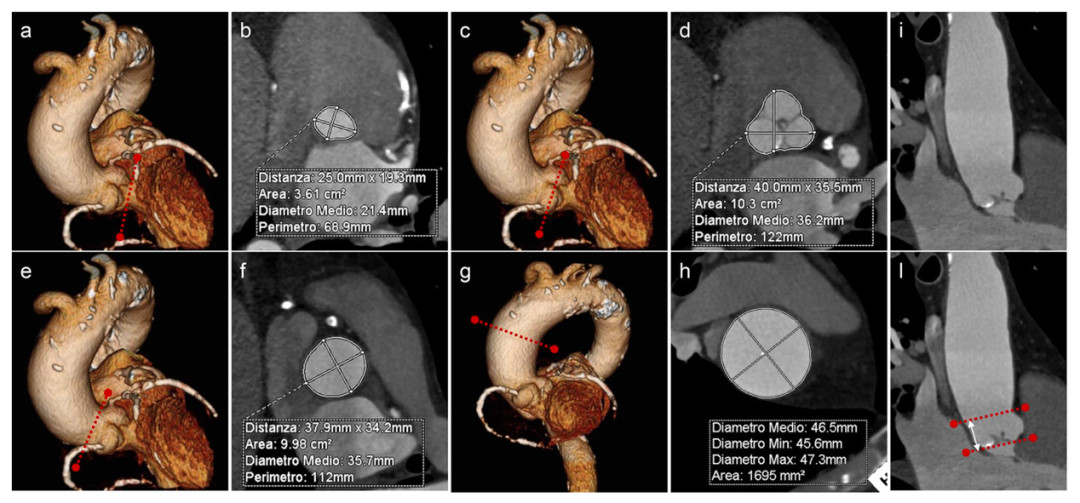

图1: 通过正交的三维重建图像(如3D VR图像(a, c, e, g)所示)测量不同解剖水平的主动脉管腔尺寸,分别为主脉瓣环(a, b), Valsalva窦(c, d),窦管交界处(e, f),升主动脉中点处(g, h)以及测量窦管交界处的高度(i, l)。